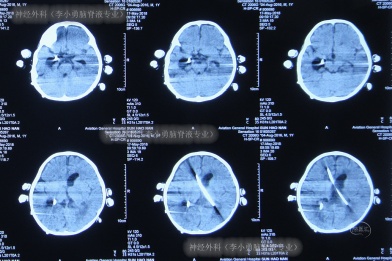

入院当天查头部CT示脑室粘连,右侧侧脑室积脓,左侧脑室扩张明显,脑室旁水肿,右侧侧脑室Ommaya囊植入术后,右侧侧腹部外引流术后(图-17)。

图-17:2018年3月26日入院时头部CT

入院次日即2018年3月27日,进行了开颅脑室探查术+透明隔造瘘术+双侧侧脑室腹壁外引流术;术后当天查CT示脑室缩小,引流管位置良好(图-18)。

图-18:2018年3月27日术后CT